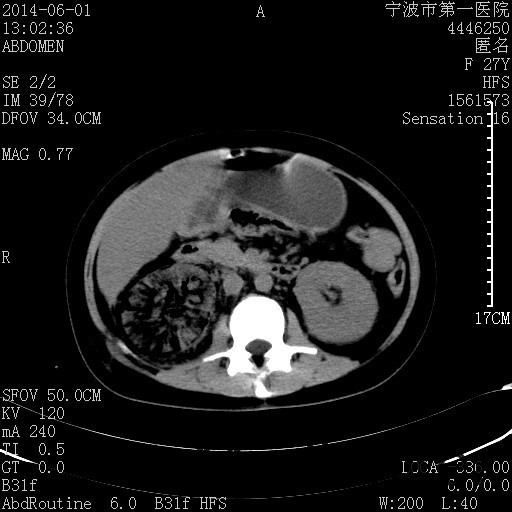

患者,女,27岁,因“右下腹疼痛伴呕吐2天”入院 患者无明显诱因出现右下腹疼痛伴呕吐、发热,体温最高39度,急诊CT示:右肾集气,考虑气性肾盂肾炎。

查体: 右肾区叩击痛,右下腹压痛,无反跳痛。 辅助检查: 空腹血糖9.7mmo/L,餐后血糖18mmol/L 血常规:白细胞 11.3*109/L, 中性百分比 77.4%, 血红蛋白 8g/L, 血小板 319*109/L 尿常规 WBC+++ 生化:白蛋白 37.5g/L,肝肾功能正常 泌尿系CT:右肾集气

诊断为“气性肾盂肾炎,感染性休克,糖尿病酮症酸中毒” 血、尿、脓液培养均示“克雷伯杆菌” 入院第2天行“右双J管置入术” 入院第3天、7天行“右肾穿刺造瘘术” 入院1月行“右肾切除术” 术后顺利康复出院。